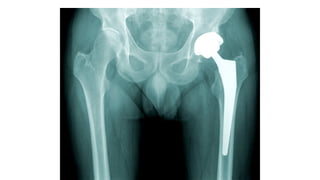

This document discusses femoral fractures, categorized by their location and severity, with classifications such as Garden classification. It outlines the types of fractures, including valgus impacted, non-displaced, partially displaced, and fully displaced, along with their surgical treatment options. Additionally, it briefly describes distal femur fractures, which occur just above the knee joint.